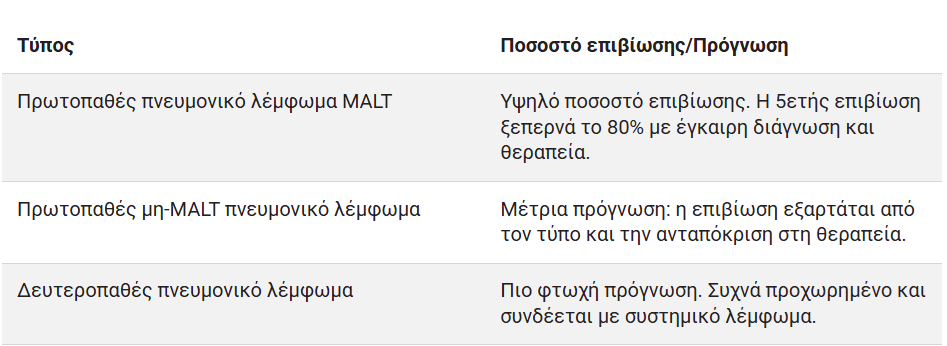

Πνευμονικό λέμφωμα: Προσδόκιμο ζωής με βάση τον τύπο

Η πρόγνωση ποικίλλει ευρέως ανάλογα με τον τύπο και το στάδιο του πνευμονικού λεμφώματος:

Παράγοντες όπως η ηλικία, η συνολική υγεία και η ανταπόκριση στη θεραπεία παίζουν καθοριστικό ρόλο στον καθορισμό του προσδόκιμου ζωής.